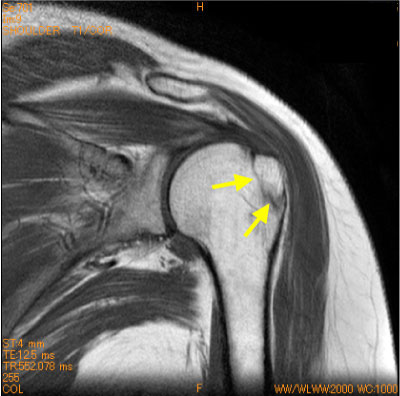

上腕骨頭不完全骨折-肩関節MRI-

50代女性、道路で転倒、単純X線写真では骨折は不明。

上腕骨大結節の通常は、骨折は直接外力によるもであるが、安静が不十分であると、骨折部が腱板に牽引による変位を生じて、後遺症を残す。

しばしば筋挫傷を伴っている。